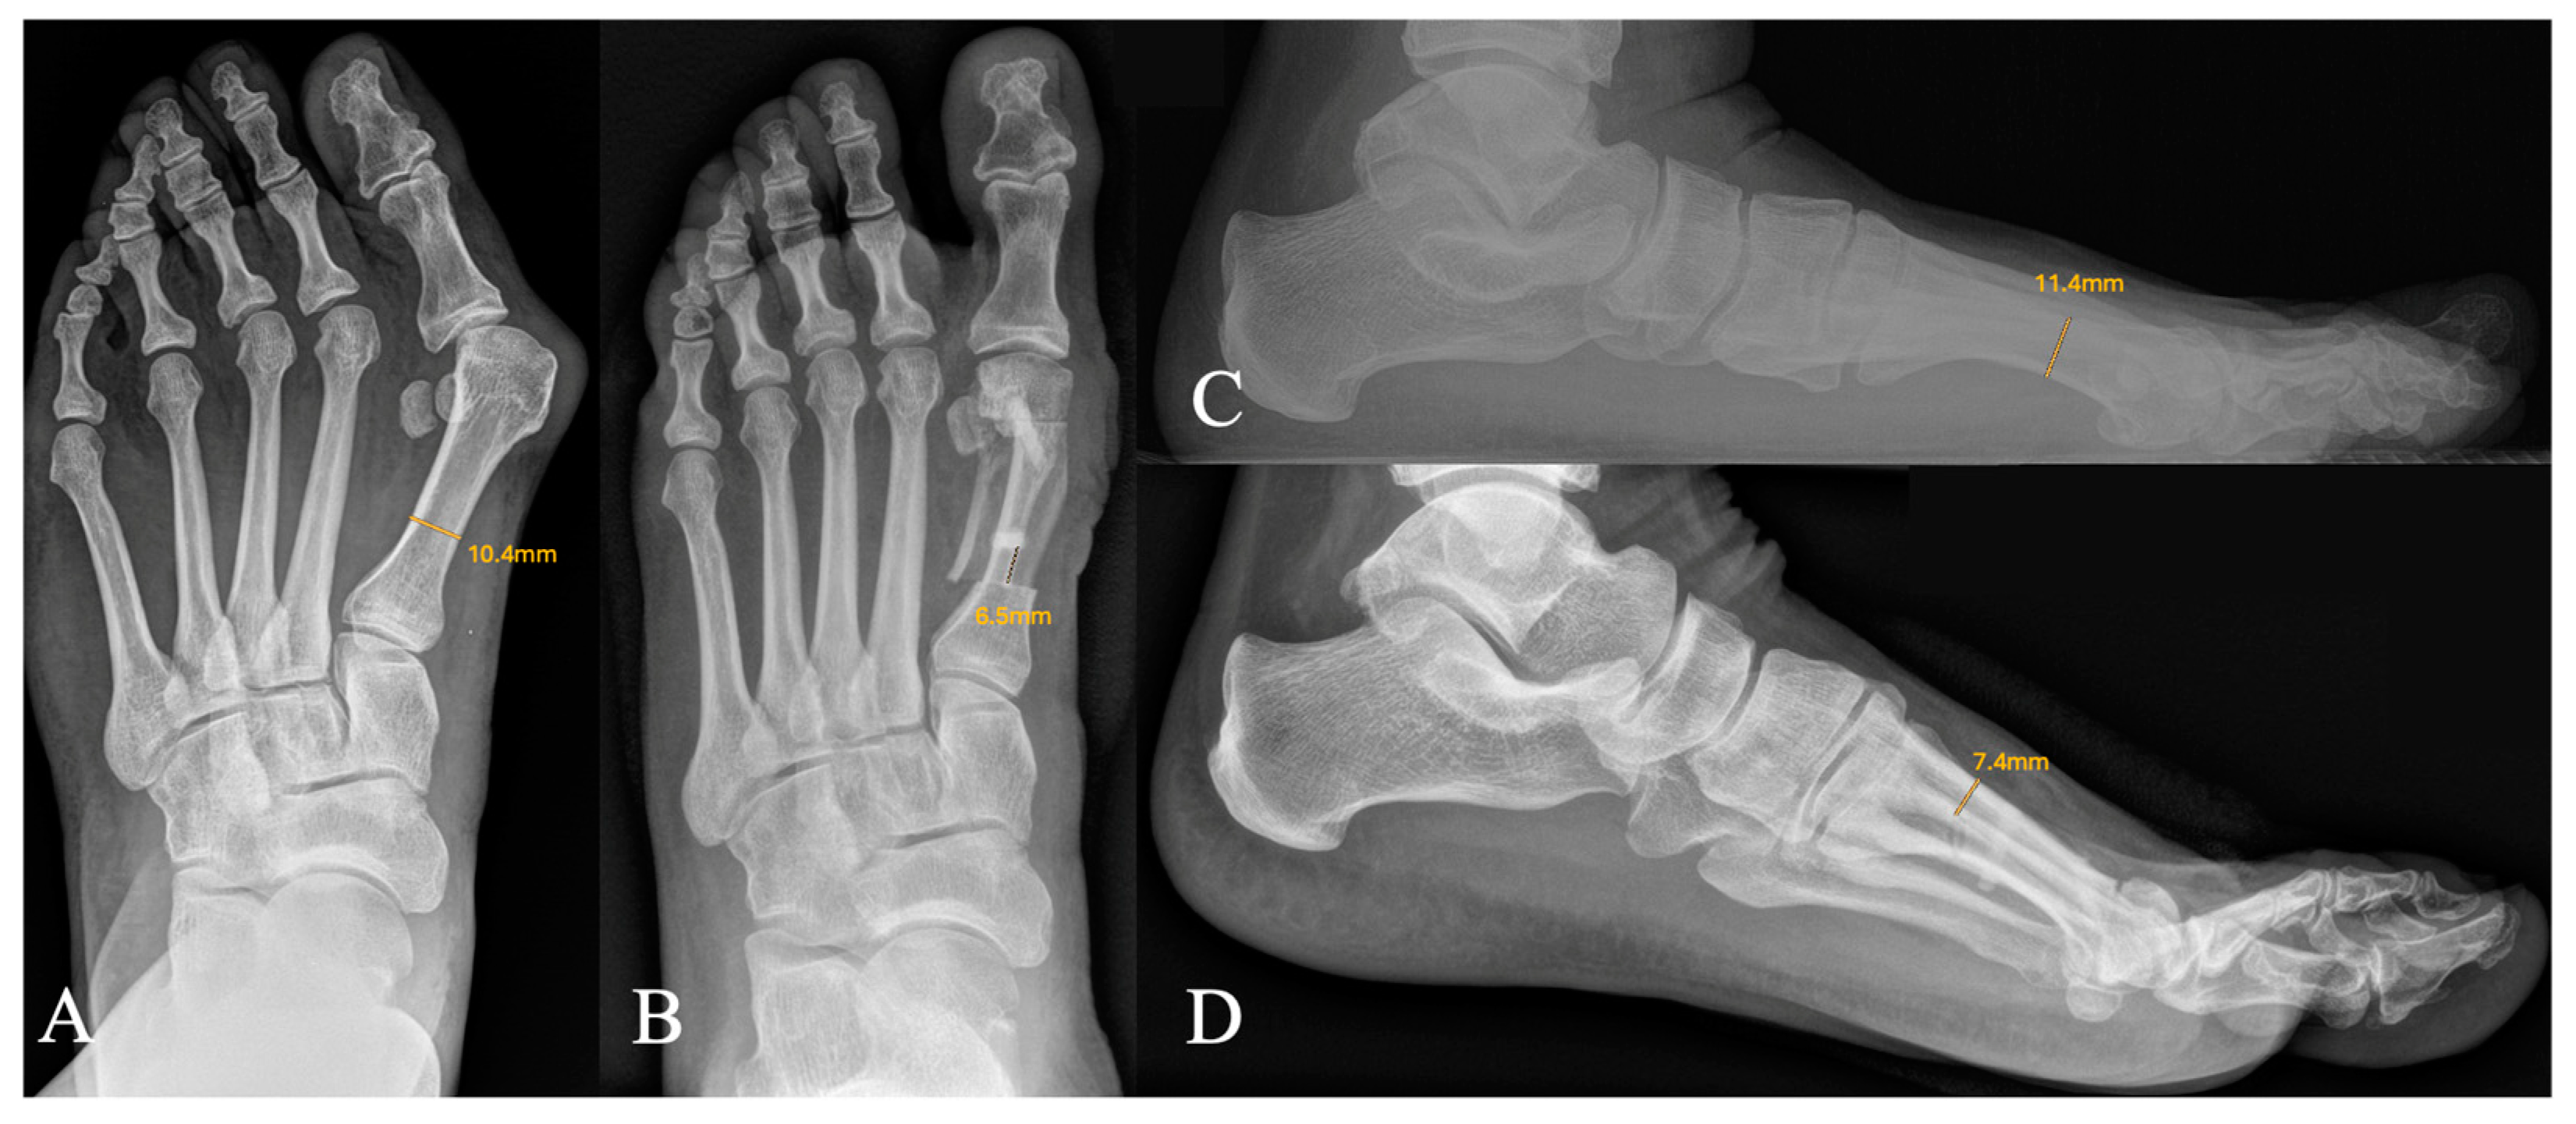

Radiological Measurements

| Distance proximal osteotomy to bone screw | 4.3 (±1.5) mm | 5.8 (±1.6) mm | 0.044 |

| Depth of dorsal-bone bridge | 5.0 (±0.82) mm | 7.4 (±0.90) mm | <0.001 |